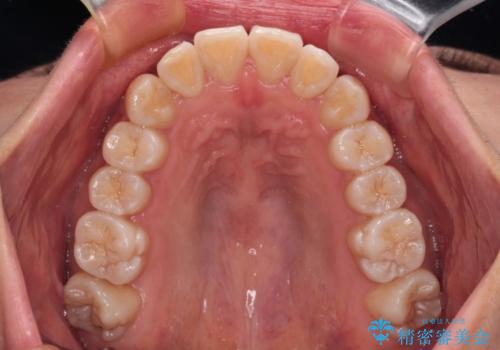

カリエールディスタライザーを併用したことで、確実かつ短期間で治療を終えることができました。